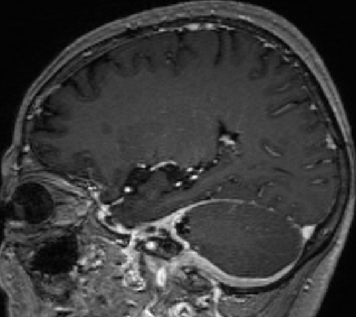

2014-10-17 CT

仍时有前额部疼痛,程度轻,调压190—200